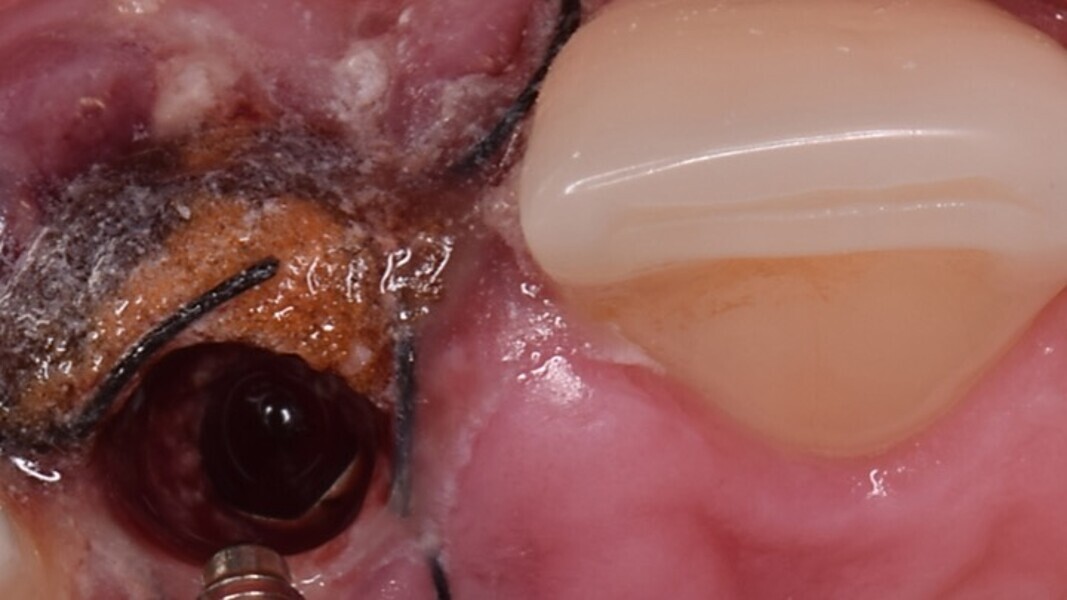

Figura 4. Exodoncia del diente.

Figura 8. Esperamos a que la superficie del implante esté siempre cubierta por un coágulo de sangre antes de adaptar el material encima de éste.